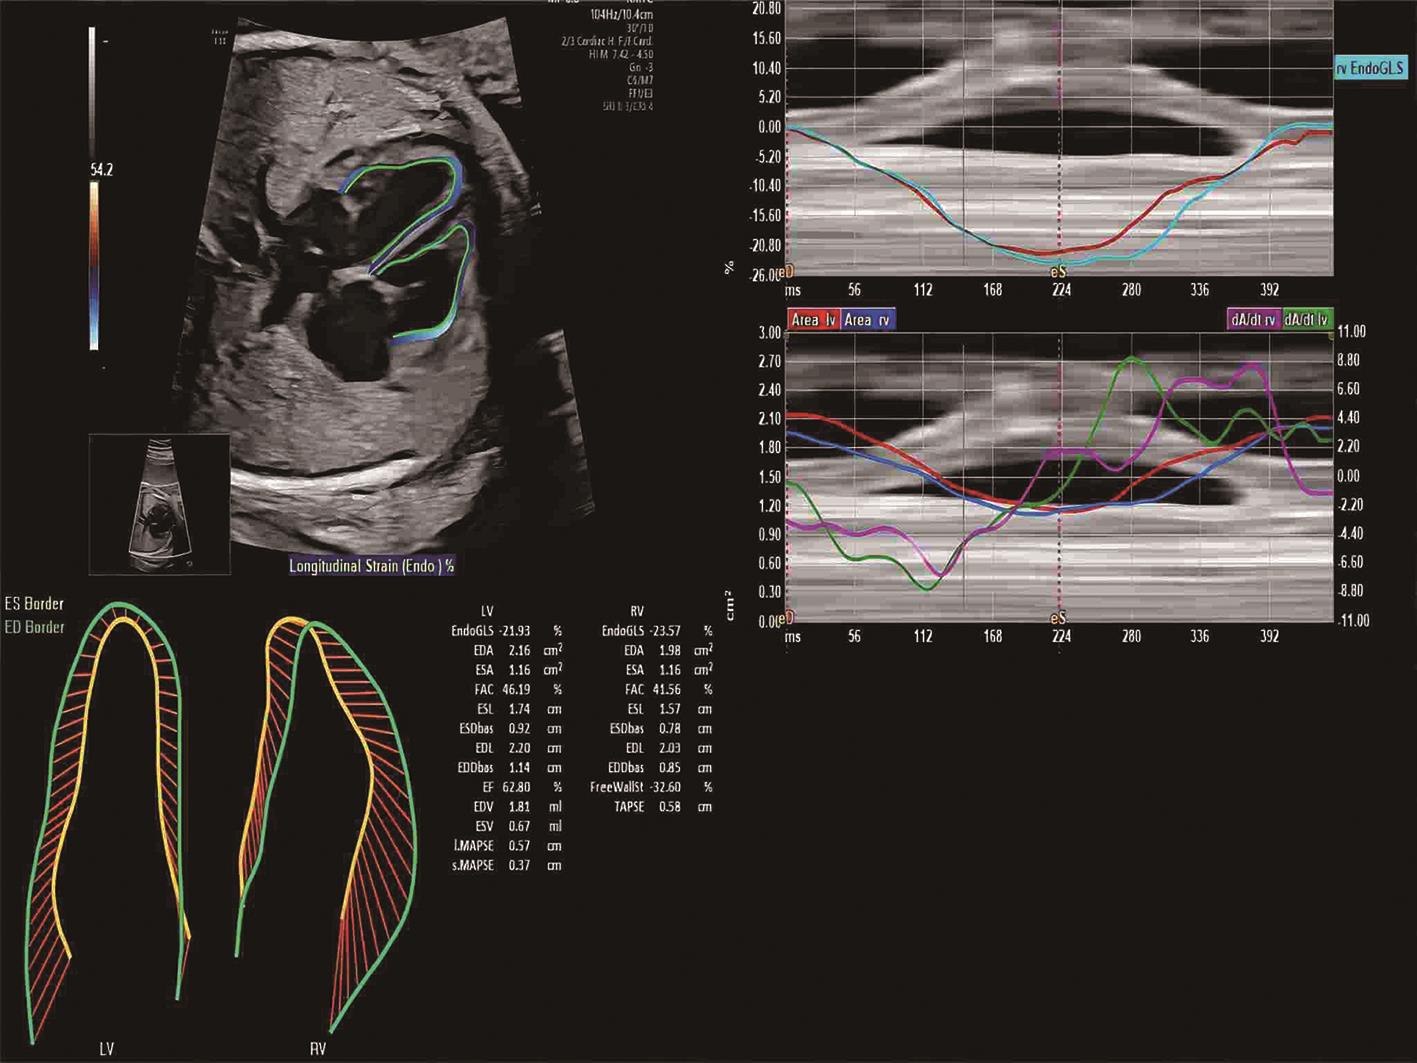

• 胎儿心脏定量分析技术评价妊娠期肝内胆汁淤积症孕妇胎儿心室收缩功能

2024, 49(1):85-90. DOI: 10.13406/j.cnki.cyxb.003377

摘要 (50) HTML (24) PDF 1.70 M (137) 评论 (0) 收藏

摘要:目的 探讨妊娠期肝内胆汁淤积症(intrahepatic cholestasis of pregnancy,ICP)对胎儿心室收缩功能的影响,为临床早期发现ICP胎儿心功能异常提供依据。方法 选取2022年7月至2023年4月于川北医学院附属医院就诊孕妇67例,孕周27~40周,其中ICP孕妇29例(ICP组),正常孕妇38例(对照组)。应用胎儿心脏定量分析(fetal heart quantification,Fetal HQ)软件测量胎儿心室收缩功能,包括纵向收缩功能:左、右心室整体纵向应变(global strain,GLS)、间隔壁应变(sept wall strain,SWS)、侧壁应变(free wall strain,FWS);横向收缩功能:左、右心室24节段短轴缩短率(fractional shortening,FS);整体收缩功能:左、右心室面积变化分数(fetal area change,FAC)、左心室射血分数(ejection fraction,EF)。结果 ICP组纵向收缩功能指标左、右心室GLS、SWS、FWS均低于对照组,差异有统计学意义(P<0.05);两组间横向收缩功能指标左、右心室24节段FS比较,差异均无统计学意义(P>0.05);ICP组整体收缩功能指标左、右心室FAC均低于对照组,差异有统计学意义(P<0.05),而两组间左心室EF比较,差异无统计学意义(P>0.05)。结论 在宫内高胆汁酸环境下,ICP胎儿心脏左、右心室整体及纵向收缩功能明显受损,横向收缩功能未见明显改变;并且与传统心脏功能评价指标左心室EF相比,FAC可以更加敏感地反映胎儿心脏整体功能的改变。